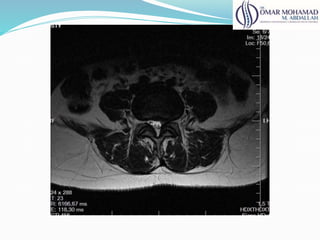

Rnm

● Melhor avaliação do disco e estruturas neurais;

● 100% de alt acima de 50 anos (lombar)

● 60% de alt acima de 60 anos (cervical)

● Correlacionar os achados com clínica

● Avalia: estabilidade, compressão e deformidades

61

Rnm ● Melhor avaliaçãodo disco e estruturas neurais; ● 100% de alt acima de 50 anos (lombar) ● 60% de alt acima de 60 anos (cervical) ● Correlacionar os achados com clínica ● Avalia: estabilidade, compressão e deformidades 61